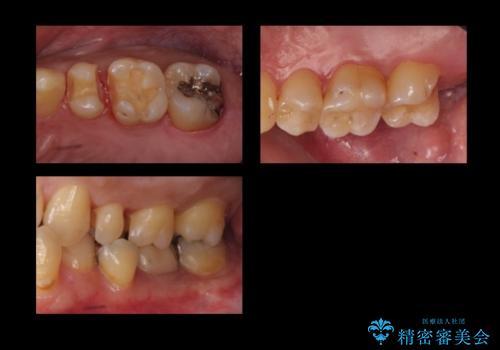

奥歯の詰め物のやりかえ セラミックインレー、ゴールドインレー

- 上の奥歯の詰め物が合っていないため、やりかえを行いました。

- 20万円 内訳 左上56:emaxインレー7万円x2 、左上7:PGAインレー6万円 (税別)費用は治療当時の料金となります

上の一番奥の歯は、一番目立たない場所なので(他人から見えない)、ゴールドインレーでも目立ちません。

セラミックインレーでは割れやすい大きさの虫歯または、歯が薄くなって被せなければいけないような場合でも、金属(ゴールド)は耐久性があり、クラウン(被せ物)にしなくて済みます。